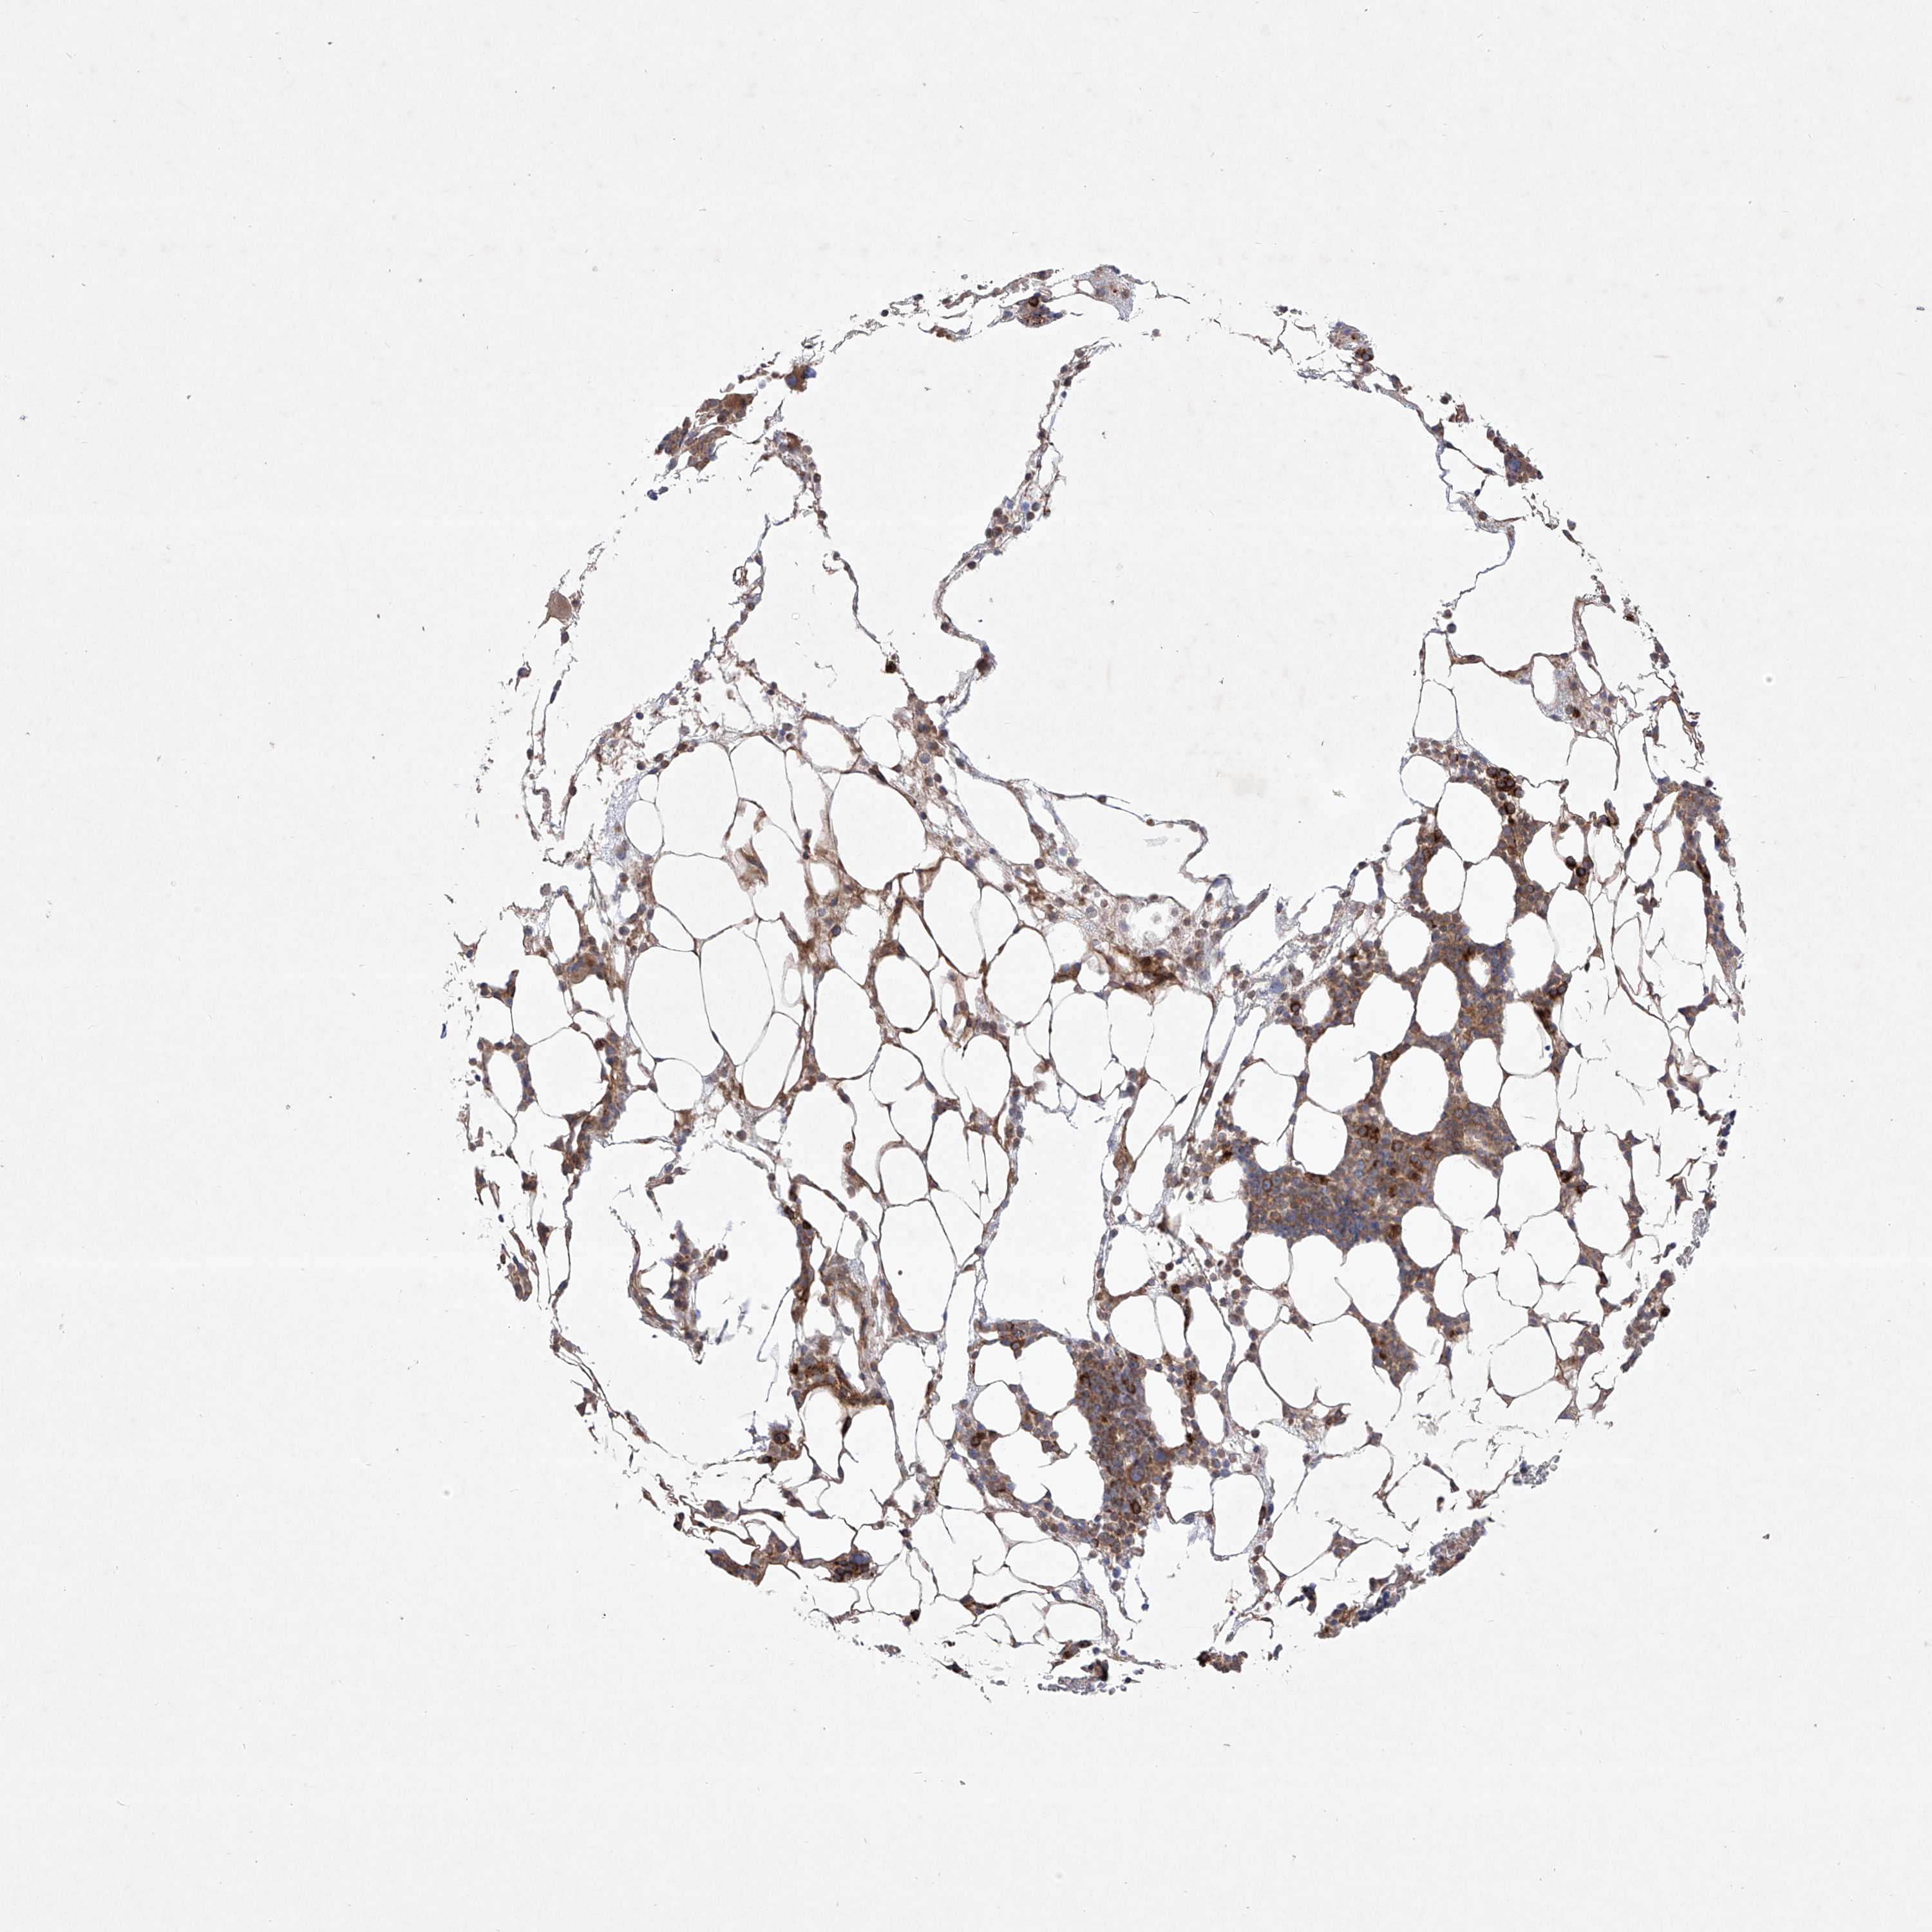

BONE MARROW - Antibody stainingi

Antibody staining in the annotated cell types in the current human tissue is reported as not detected, low, medium, or high, based on conventional immunohistochemistry profiling in selected tissues. This score is based on the combination of the staining intensity and fraction of stained cells.

Each image is clickable and will lead to virtual microscopy that enables deeper exploration of all samples and also displays staining intensity scores, fraction scores and subcellular localization as well as patient and tissue information for each sample.

Antibody HPA030817Antibody HPA030818

Hematopoietic cells MediumLow